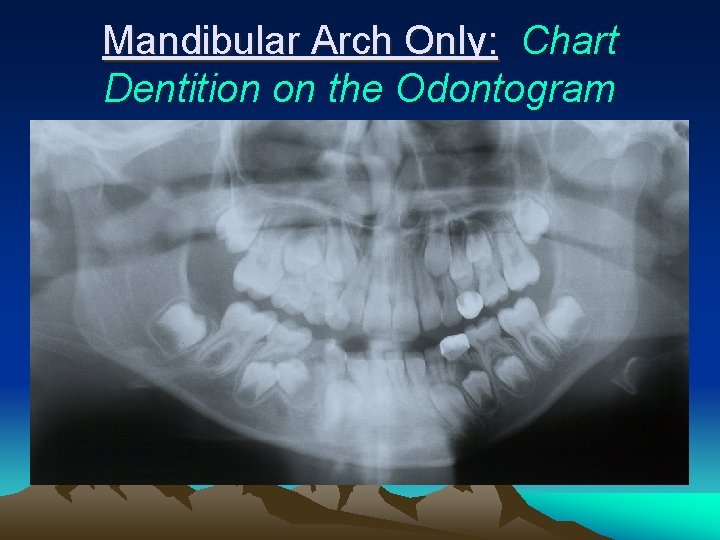

Mandibular Arch Only: Chart Dentition on the Odontogram

Ali • Mandibular Arch Only : Chart abnormalities and pathology (including caries ) from the Panorex and Bite Wing Radiographs

Ali • Teeth Present: 19, K, L, M, 23, 24, 25, 26, R, S, T, 30 Restorations: SSC #L Pathology/Caries: #L and #S abscessed, #28 severely ectopic.